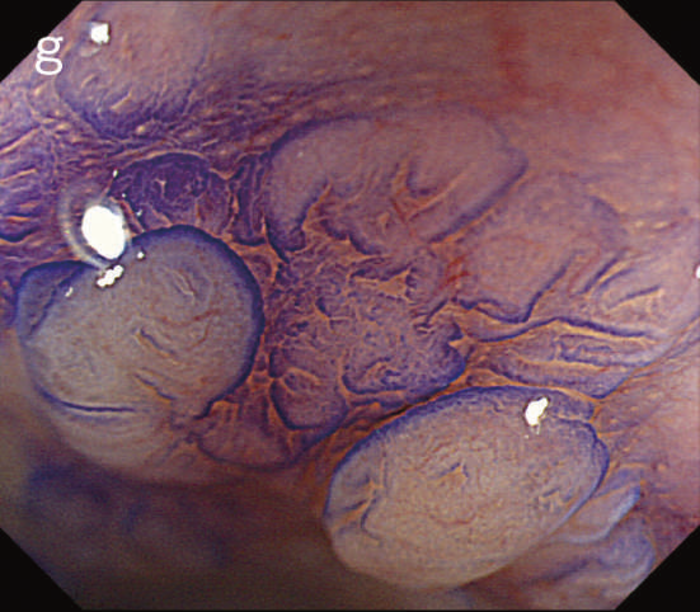

図6 UC関連LGDの内視鏡所見

- 白色光像:直腸(下部直腸)に色調変化は乏しく,微小な隆起を複数認めた。背景粘膜は寛解期にあった。

- NBI非拡大像:Brownishな領域が明らかとなった。

- 色素内視鏡像:病変辺縁が明瞭な微小な隆起を複数伴う表面平坦型病変。

- NBI拡大像:口径整でらせん状の微小血管と絨毛状の表面構造を認めた。

- pit pattern像:小型の類円形,管状pitを認めた。